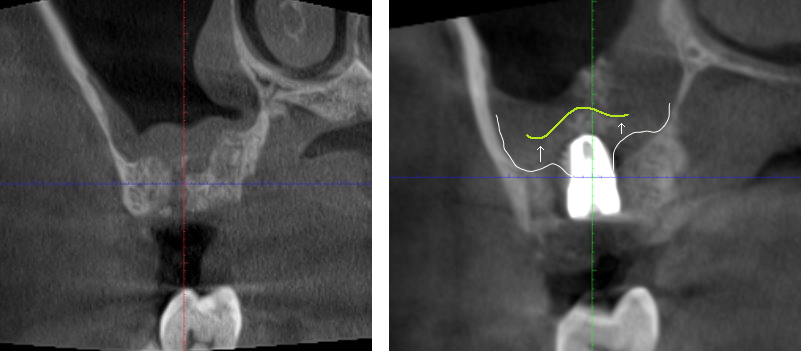

術前X光片

上顎竇增高 前後比較